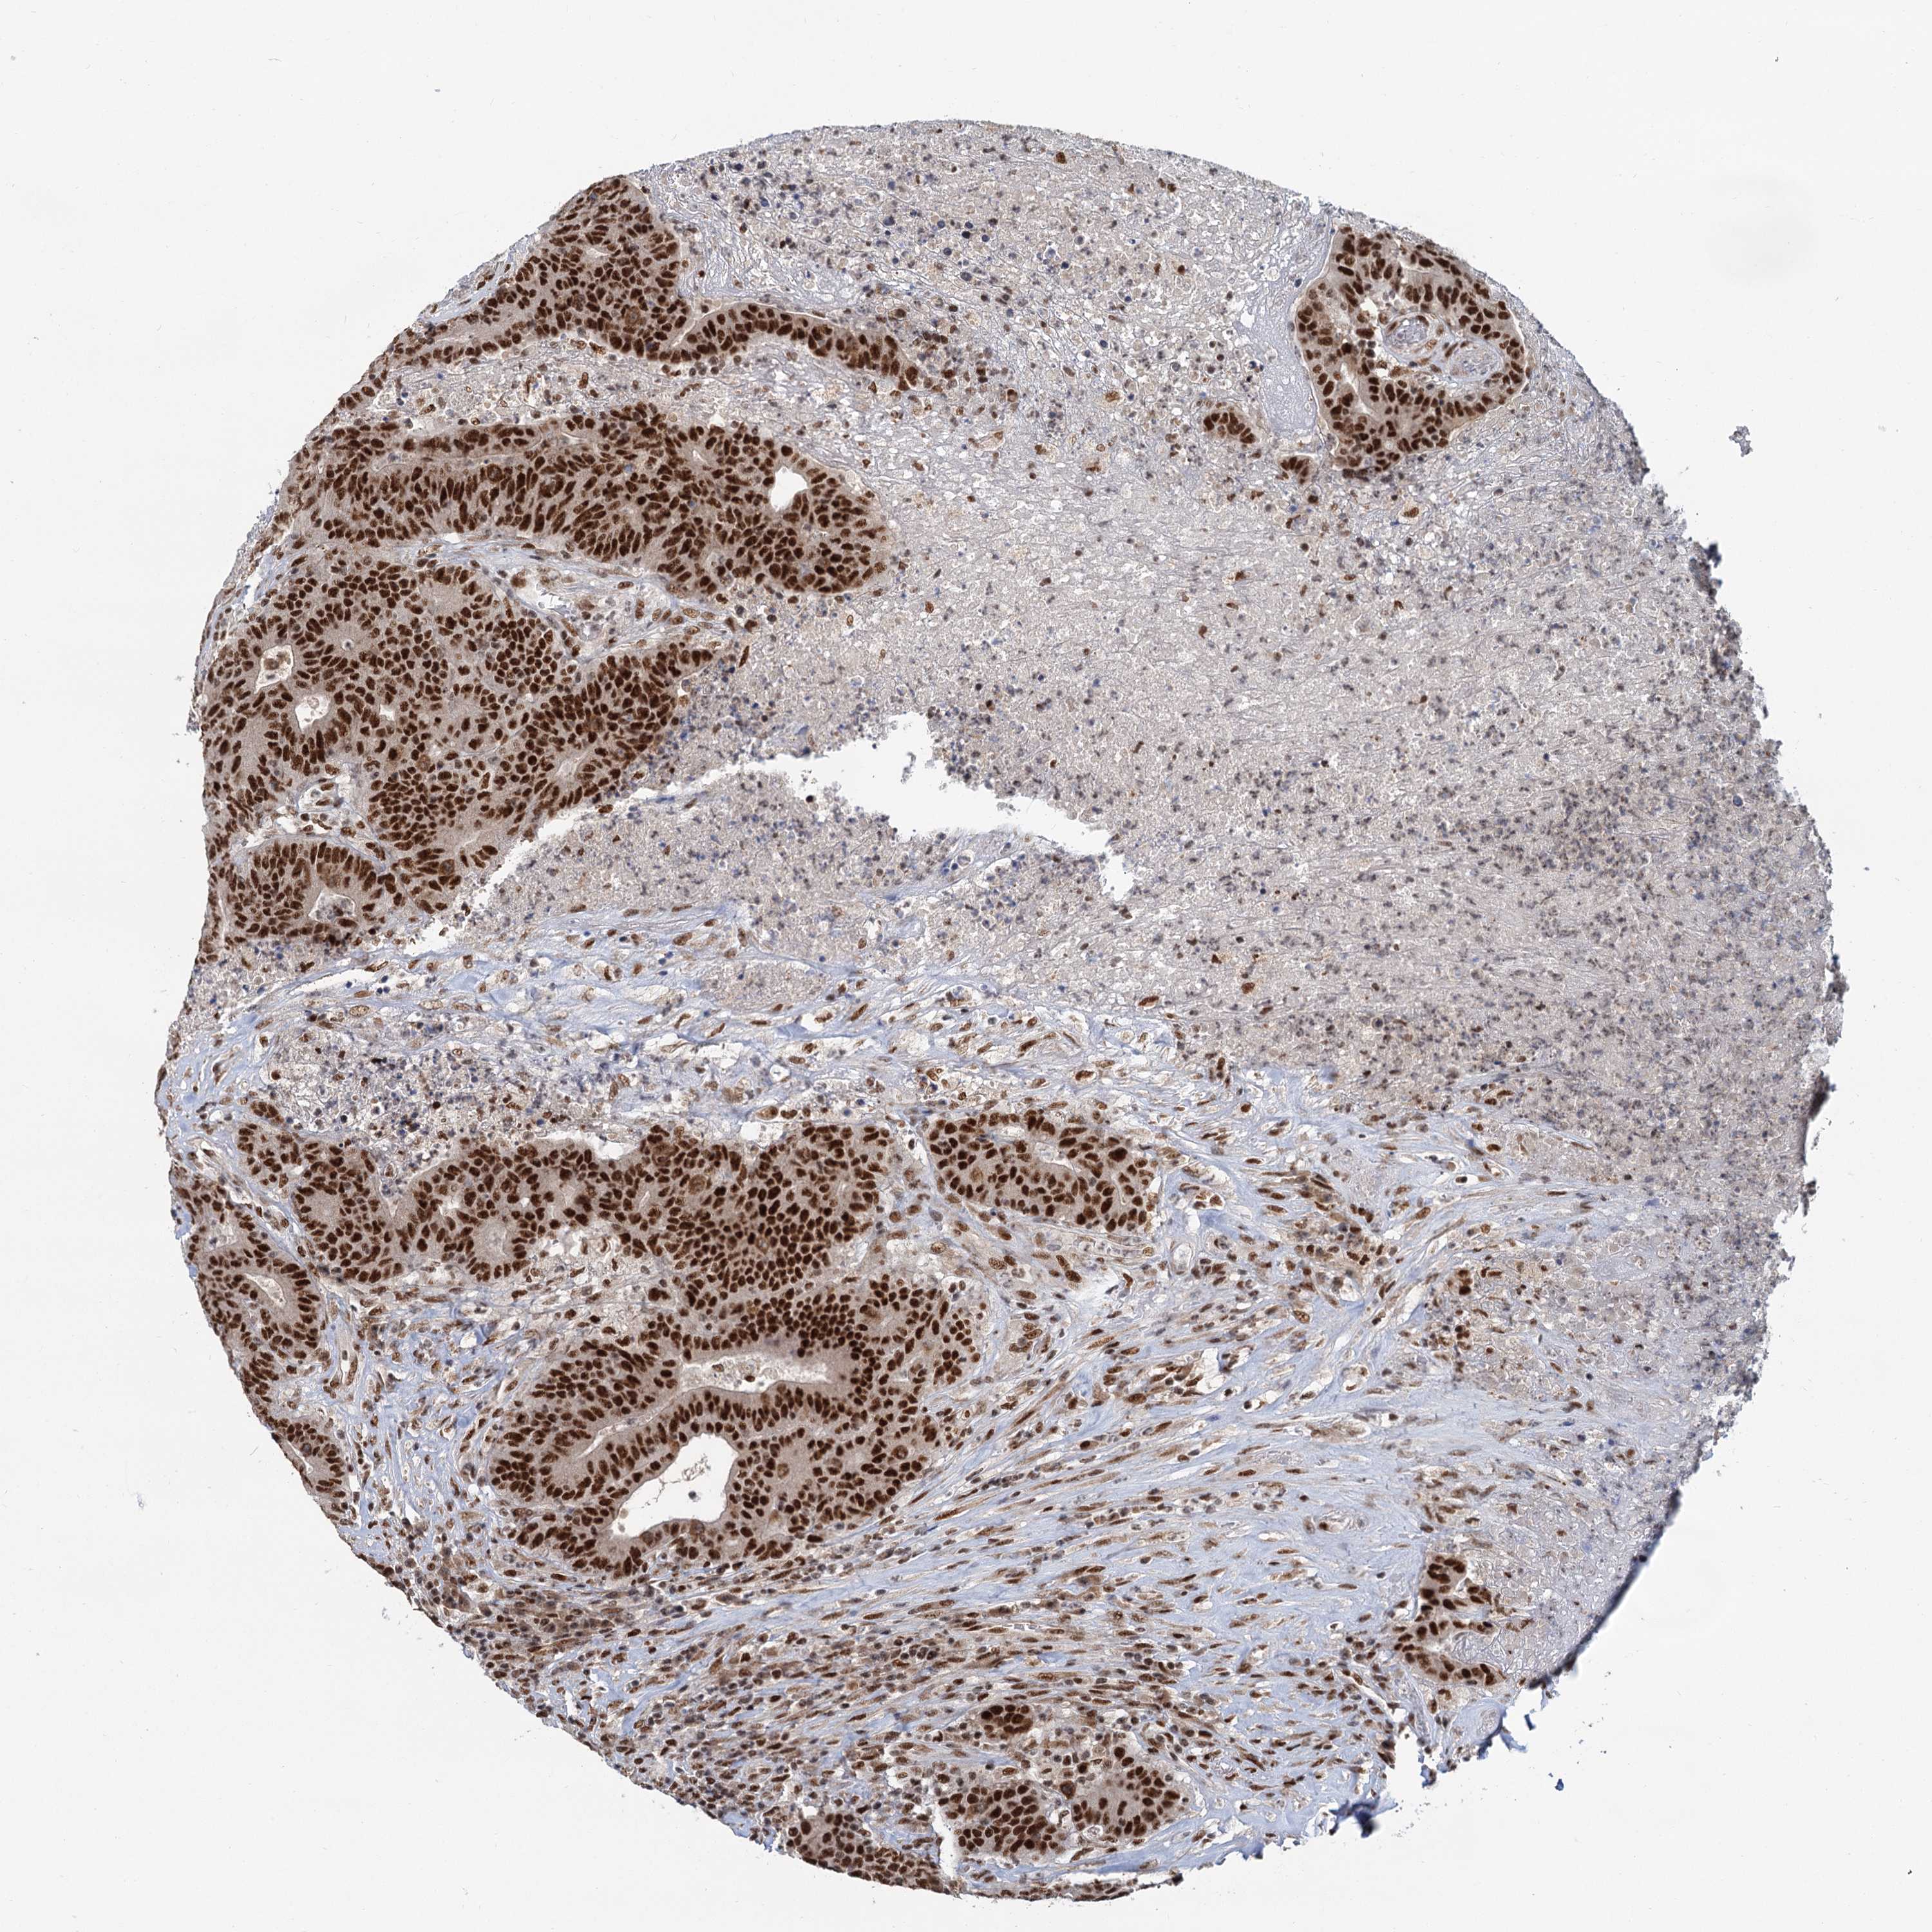

CANCER COLORECTAL CANCER Show tissue menu

Colorectal cancer

Human cancer

Colon adenocarcinoma